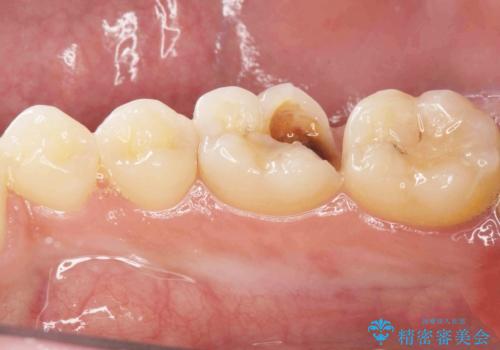

[ 深い虫歯・根管治療・セラミッククラウン ]複合した問題を持った虫歯治療

![[ 深い虫歯・根管治療・セラミッククラウン ]複合した問題を持った虫歯治療の症例 治療後](https://seimitsushinbi.jp/wp/wp-content/uploads/2022/09/bd017e5dbd742f9bb33f09d39c8f1b52-500x350.jpg?v=1663667487)